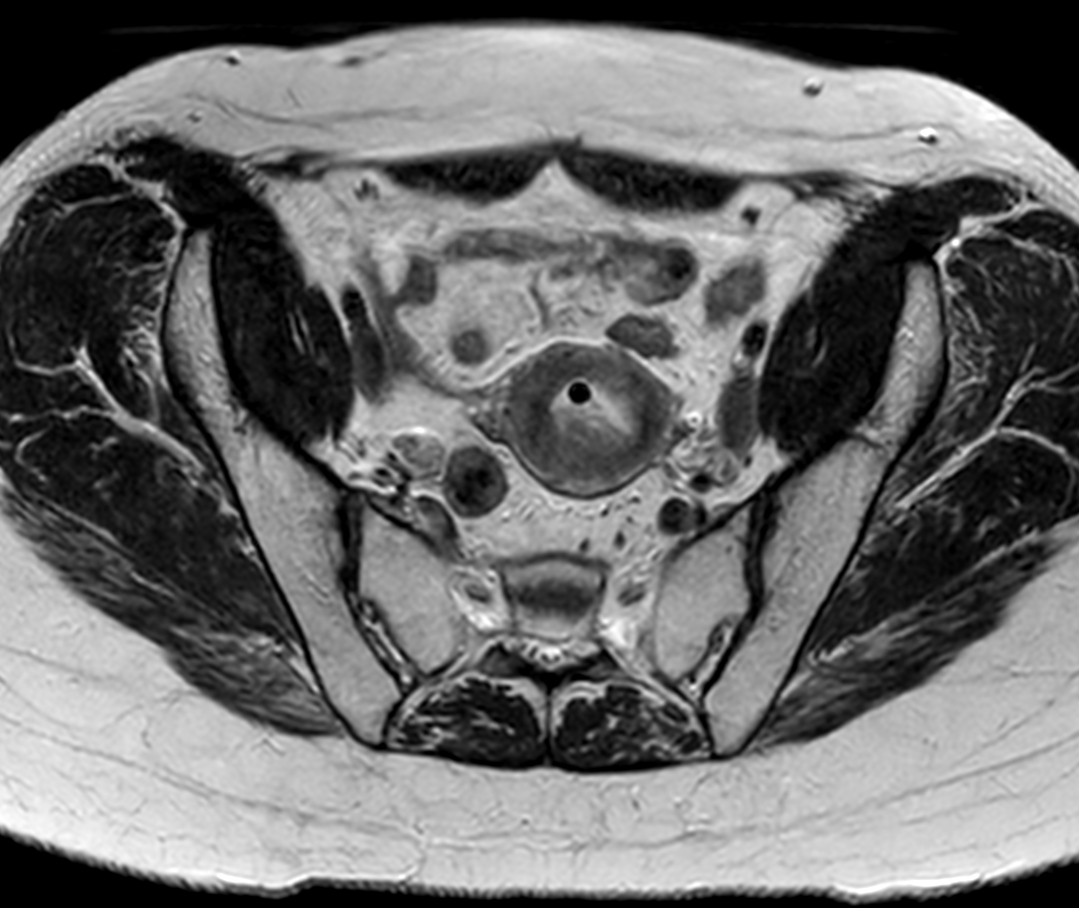

Patient with cervical cancer referred for MR-guided brachytherapy. MR imaging on Ingenia 1.5T with tandem-ring applicator in place for brachytherapy planning.

Axial oblique 2D T2w TSE